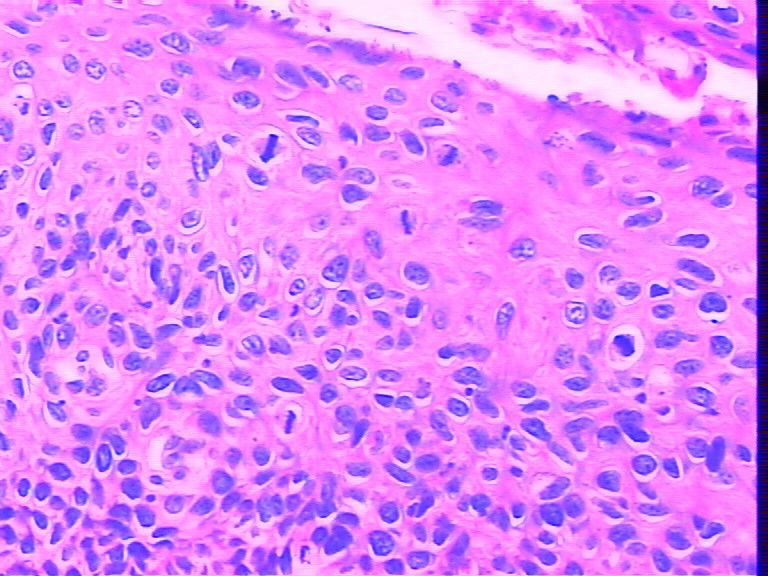

请问有没有这种说法?就拿下面那副图看看,可以打到cin II ,但听说套用这种说法,打CIN I 比较好,是不是真的这样?

名称:病变超过2/3,够II级